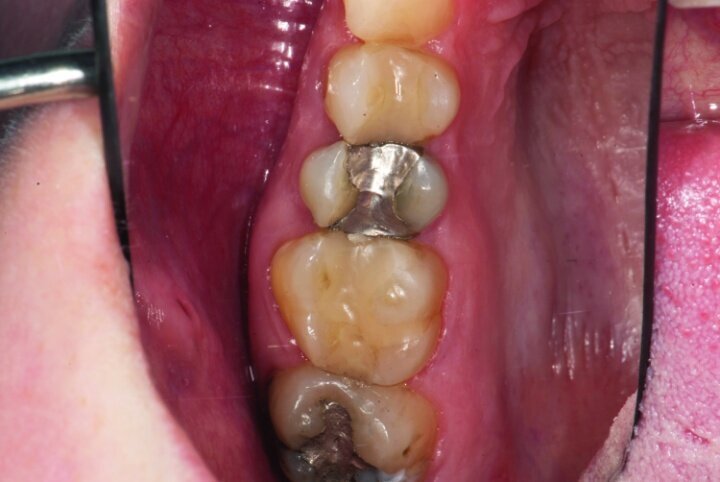

This patient presented for restorations of teeth #3 and #4 (Fig. 1a). Because of the size of the existing restorations, these teeth were diagnosed as structurally compromised (Figs. 1b, c). The prognosis without treatment was fair.

After gross occlusal reduction was completed, the remaining enamel ring was measured (Figs. 9a, b). The enamel rings were noted to be 1.5 mm, and the teeth were prepared for adhesively retained restorations. If the enamel rings were less than 1 mm, the teeth would have been prepared on the axial walls to create retention for cohesively retained crowns.

The remainder of the existing composite resin in #3 and the amalgam in #4 were removed. The occlusal surfaces of the preparations were blended into the interproximal areas using a KS2 bur to create smooth preparations (Figs. 10–15c). There was no retention or resistance form prepared to retain the restorations.